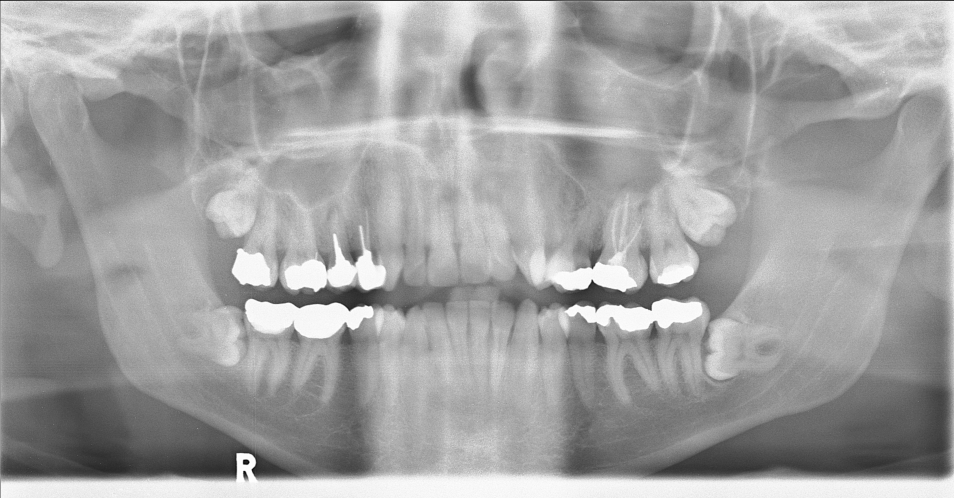

| 27 |

Abnormal fr lt mand condyle |

Abnormal Left mandibular condyle fracture |

Correct |